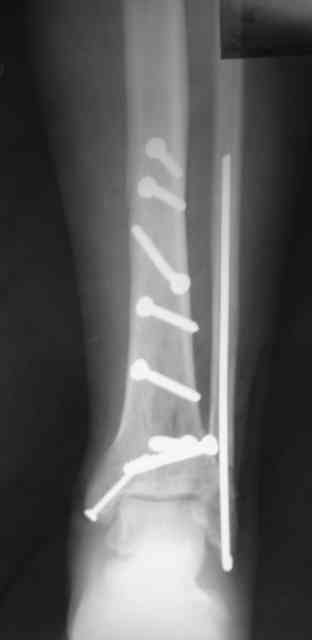

Сегодня прооперировали. Длительность 4-50. Начали как и говорил сверху вниз линейным разрезом - фиксация задне-латерального отломка к проксимальному 2мя винтами, затем "прилепили" к ним передне-медиальный (пришлось повозиться - была интерпозиция и довольно "сложный" винт) - к проксимальному 1 винтом и к задне-латеральному 1 винтом.Кстати на фото видно - у передне-медиального отломка еще осколок в области сустава, несколько смят. Далее началось веселье - второй доступ - задне-наружный к латеральной лодыжке и заднему краю, но оказалось, что задний край больше задне-медиальный (по снимкам было непонятно). Плюс к этому репозиция его мягко говоря сложновата (больной на спине, стол низкий и не поднимается). В общем выставили, фискировали 2мя винтами, на ЭОПе вроде стал, только верх отошел. Латеральную лодыжку заведующий решил интрамедуллярно (не хотел еще винты толкать), сначала 3мм спицей - нестабильно, затем 4мм стержень (не помню по автору) - ОК (кстати в месте перелома мелкая крошка - дефект до 5х7 мм по кортикалу). Ну медиальная лодыжка стандартно - третий разрез - винт 3,5 мм. Визуально все стабильно. На Р-контроле - видна небольшая ступенька заднего края по одному из контуров.

Рентгенограммы